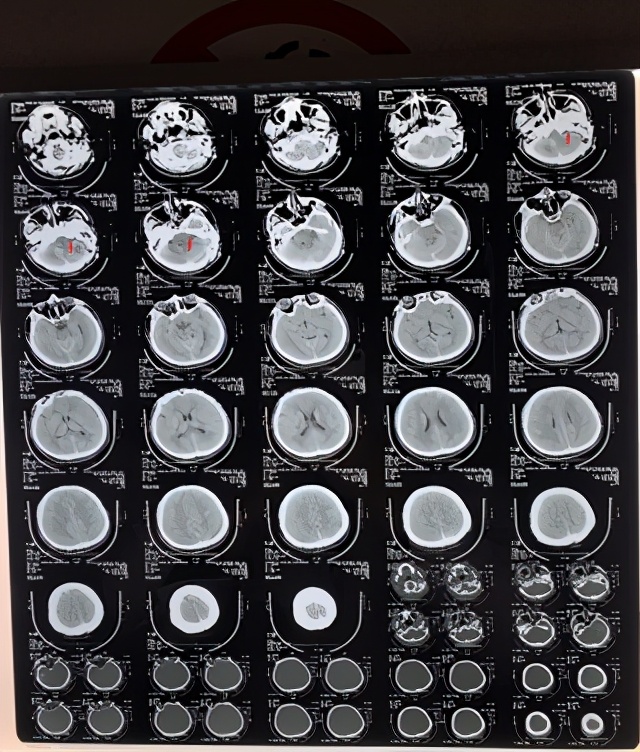

3、术前给予脑血管造影和头颅CT检查了解肿瘤血管分布及乳突情况,选择合适的手术入路。

4、根据上述检查,选择枕下乙状窦后入路肿瘤切除术。

5、术后复查CT可见肿瘤切除干净,患者自述听力恢复正常,没有耳鸣、舌麻、头晕、走路不稳等症状,没有面瘫、面部感觉异常等并发症。